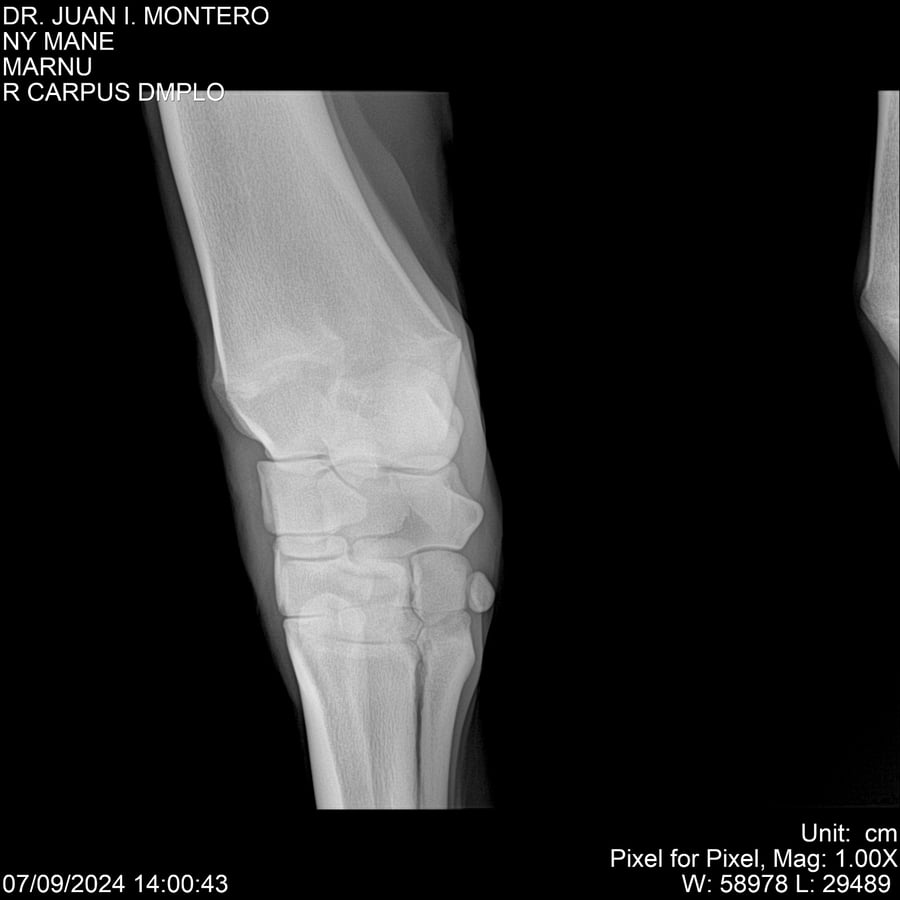

LOTE 20, NY MANE Lote Anterior Volver al remate Lote Siguiente Ficha Contacto Montevideo - Ficha del Lote Identificador: #282520 Categoría: Yeguarizos 76 Visualizaciones ClicData Contacto Empresa: Abelenda N. R., Walter Hugo Nombre*: Teléfono* : E-mail* : Mensaje Enviar Registrese gratis Este contenido Exclusivo está disponible sólo para usuarios registrados Ingresar